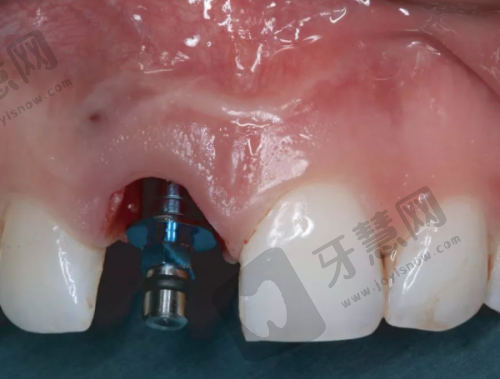

李先生实例:因意外前牙缺失,影响外貌和自信心。潘蛟南医生为其制定个性化方案,种植手术顺利,术后前牙修复美观,咀嚼功能良好,李先生对成效非常满意,自信心提升。

王女士实例:前牙龋齿多次治疗不佳,选择拔牙并进行前牙美学种植。严余飞医生手术操作精细,术后修复良好,种植后牙齿与面部协调,美观度提高,王女士重新拥有健康美丽牙齿。

种植成效:前牙美学种植注重美观与功能结合,南宁岭南口腔医生团队能根据患者面部特征和口腔情况制定个性化方案,让种植后牙齿与整体形象协调。综合来看,该项目比较划算。